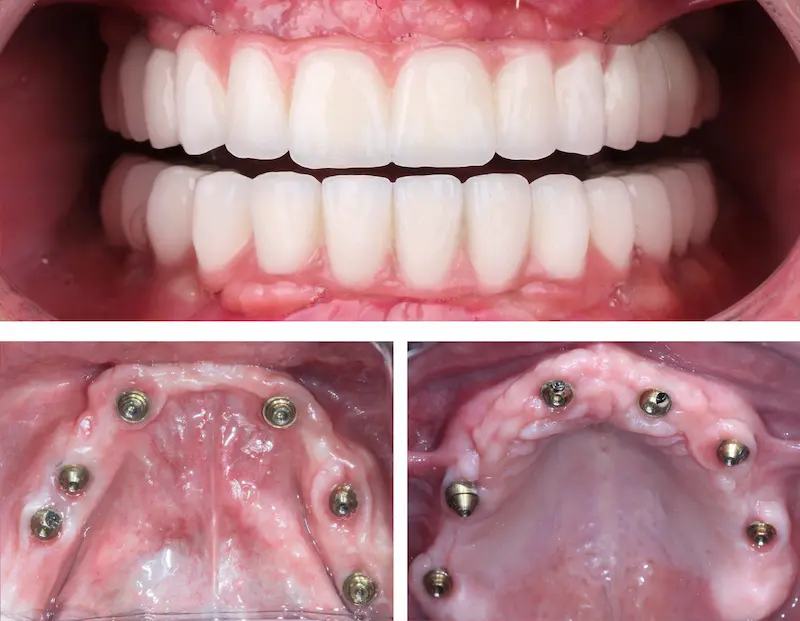

- البدء بالإجراء: بعد التخدير الموضعي أو الكامل (حسب تفضيل المريض وخطة العيادة)، يُجري الطبيب شقوقًا بسيطة في اللثة، ثم يغرس 6 زرعات مصنوعة عادةً من التيتانيوم عالي التوافق الحيوي. إذا كانت الحالة تسمح، يمكن وضع تركيبة مؤقتة بنفس اليوم أو بعد أيام قليلة (ما يعرف بـزراعة الأسنان الفورية).

- التعافي بعد زراعة الأسنان: يجب انتظار فترة تتراوح بين 3 إلى 6 أشهر لكي يندمج الزرع في العظم بشكل كامل (الاندماج العظمي). خلال هذه المدة قد تبقى تركيبات مؤقتة حتى تتحمل الزرعات الجسر النهائي.

- التحسن الجذري في المظهر: يتحدث كثيرون عن مدى انبهارهم بالنقلة الكبيرة من الابتسامة المنعدمة أو الأسنان المفقودة إلى ابتسامة كاملة جميلة.

- الانتقال من تركيبات متحركة إلى ثابتة: يعبر المرضى الذين استعملوا سابقًا الأطقم المتحركة عن سعادة بالاستقرار والنظافة الأسهل التي توفّرها الزراعة.

- الراحة أثناء المضغ: لم يعد المرضى يشعرون بالقلق من انزلاق الأطقم أو الشعور بالألم، إذ تعمل الزرعات الثابتة على تعزيز الثقة في الأكل والتكلم.